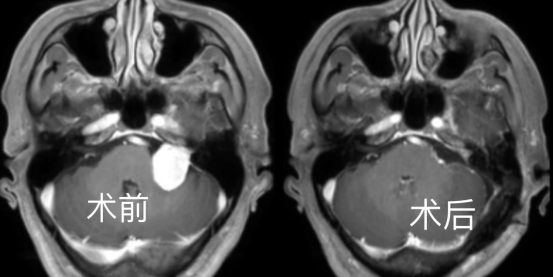

患者是 44 岁的李师傅,来之湖北红安县的工人,前 2 年发现听力下降,伴有耳鸣,当时未予以重视。就诊当地医院发现巨大右侧囊实性听神经瘤,大小约 4*3.3*4.2 cm。肿瘤压迫控制呼吸、心跳的「生命中枢」脑干,后来出现右侧肢体无力,右侧肢体肌力约 4 级。近日住入我院后,神经疾病诊疗中心王煜教授,神外金胜昔教授团队科学论证手术方案,再麻醉科胡玲教授团队精心护航下,历经 7 小时完整切除肿瘤,术后恢复良好,术后病理证实为听神经鞘瘤。